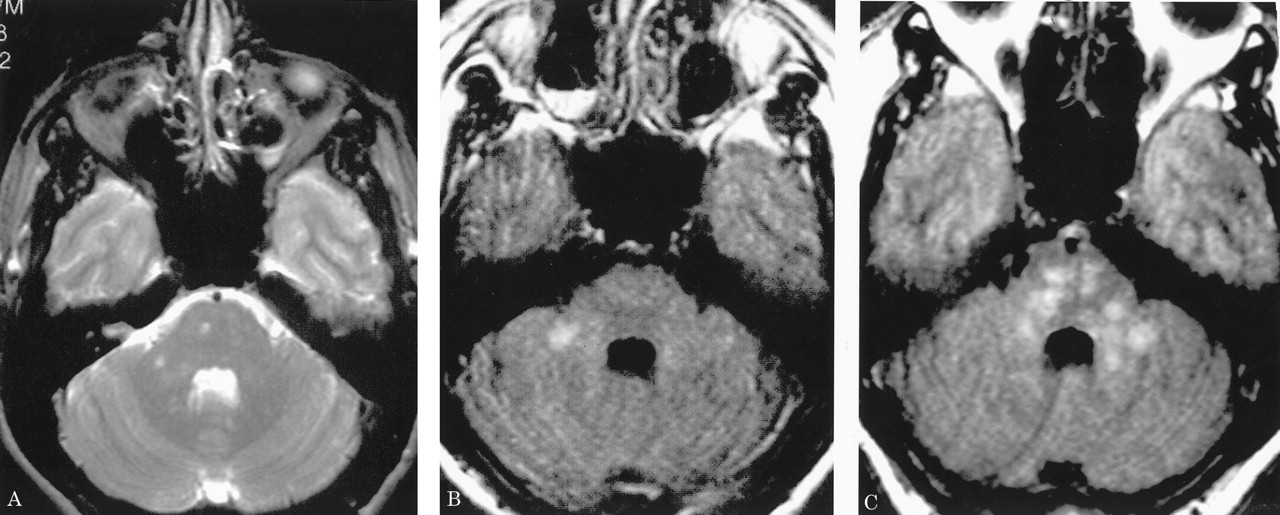

多病灶的幕上的白质病变,包括胼胝体(图1),在所有27个病人,有频繁的参与小脑,中间小脑总花梗,和脑干图1,表)。病变众多,往往是小(3 - 7毫米)但有些小病变成为支流和一些大的(> 7毫米)。19病人实质增强,当明显,导致大脑的粟粒状的外观(图2)。胼胝体的损伤通常是小的,并且涉及中央与周边的相对保留纤维;增强是变量。急性胼胝体的病变(图3)中观察到的活动脑病取而代之的是一个“充满”/穿孔先生出现在后续所有27例(图4),可能代表microinfarctions,没有出现在其他地方。胼胝体,最好在薄片(3毫米厚)矢状T1或T2矢状/质子密度加权图像,由一系列小(3毫米)中央孔相隔7毫米矢状T1和T2矢状/质子密度图像。这些扩展在整个长度的胼胝体。当急性(“雪球”)(见大图3)胼胝体的病变,慢性残余孔较大,尤其是在压部。线性缺陷有时看到的,可能反映microinfarction间接辐射在胼胝体轴突。中央孔(见图4)被认为是由于横向辐射的胼胝体轴突的微型心肌梗塞的可能性。

有深的灰色基底节和丘脑病变19病人(参见表),通常体现在T2信号强度增加,质子密度,和天赋的图像。大病变类似“巨大陷窝”43并建议纹状体外动脉增的广泛参与。三个这样的病人显示这些病变显著增强,伴随着leptomeningeal增强。实质增强(见图2)有关的大脑区域,偶尔与leptomeningeal增强(见相关表)。串行扫描被执行,增强可能是更常见。脑病减弱和病人开始恢复,只有残余病灶中央(见胼胝体的洞图4)和一些白质病变。在两个病人,增加信号强度变化在胼胝体伴随着中央胼胝体的洞在最初的MRI检查。更严重影响病人、脑和小脑萎缩随之而来。在两个这样的实例,胼胝体越来越萎缩,前面提到的胼胝体的洞几乎消失了。

在一些患者中,白质变化是最小的程度与严重程度的脑病。双倍剂量与磁化钆转移可能显示(见更广泛的变化图2),这将有助于解释这个明显的临床/差距先生。我们使用这个序列只在我们的一个病人,然而。